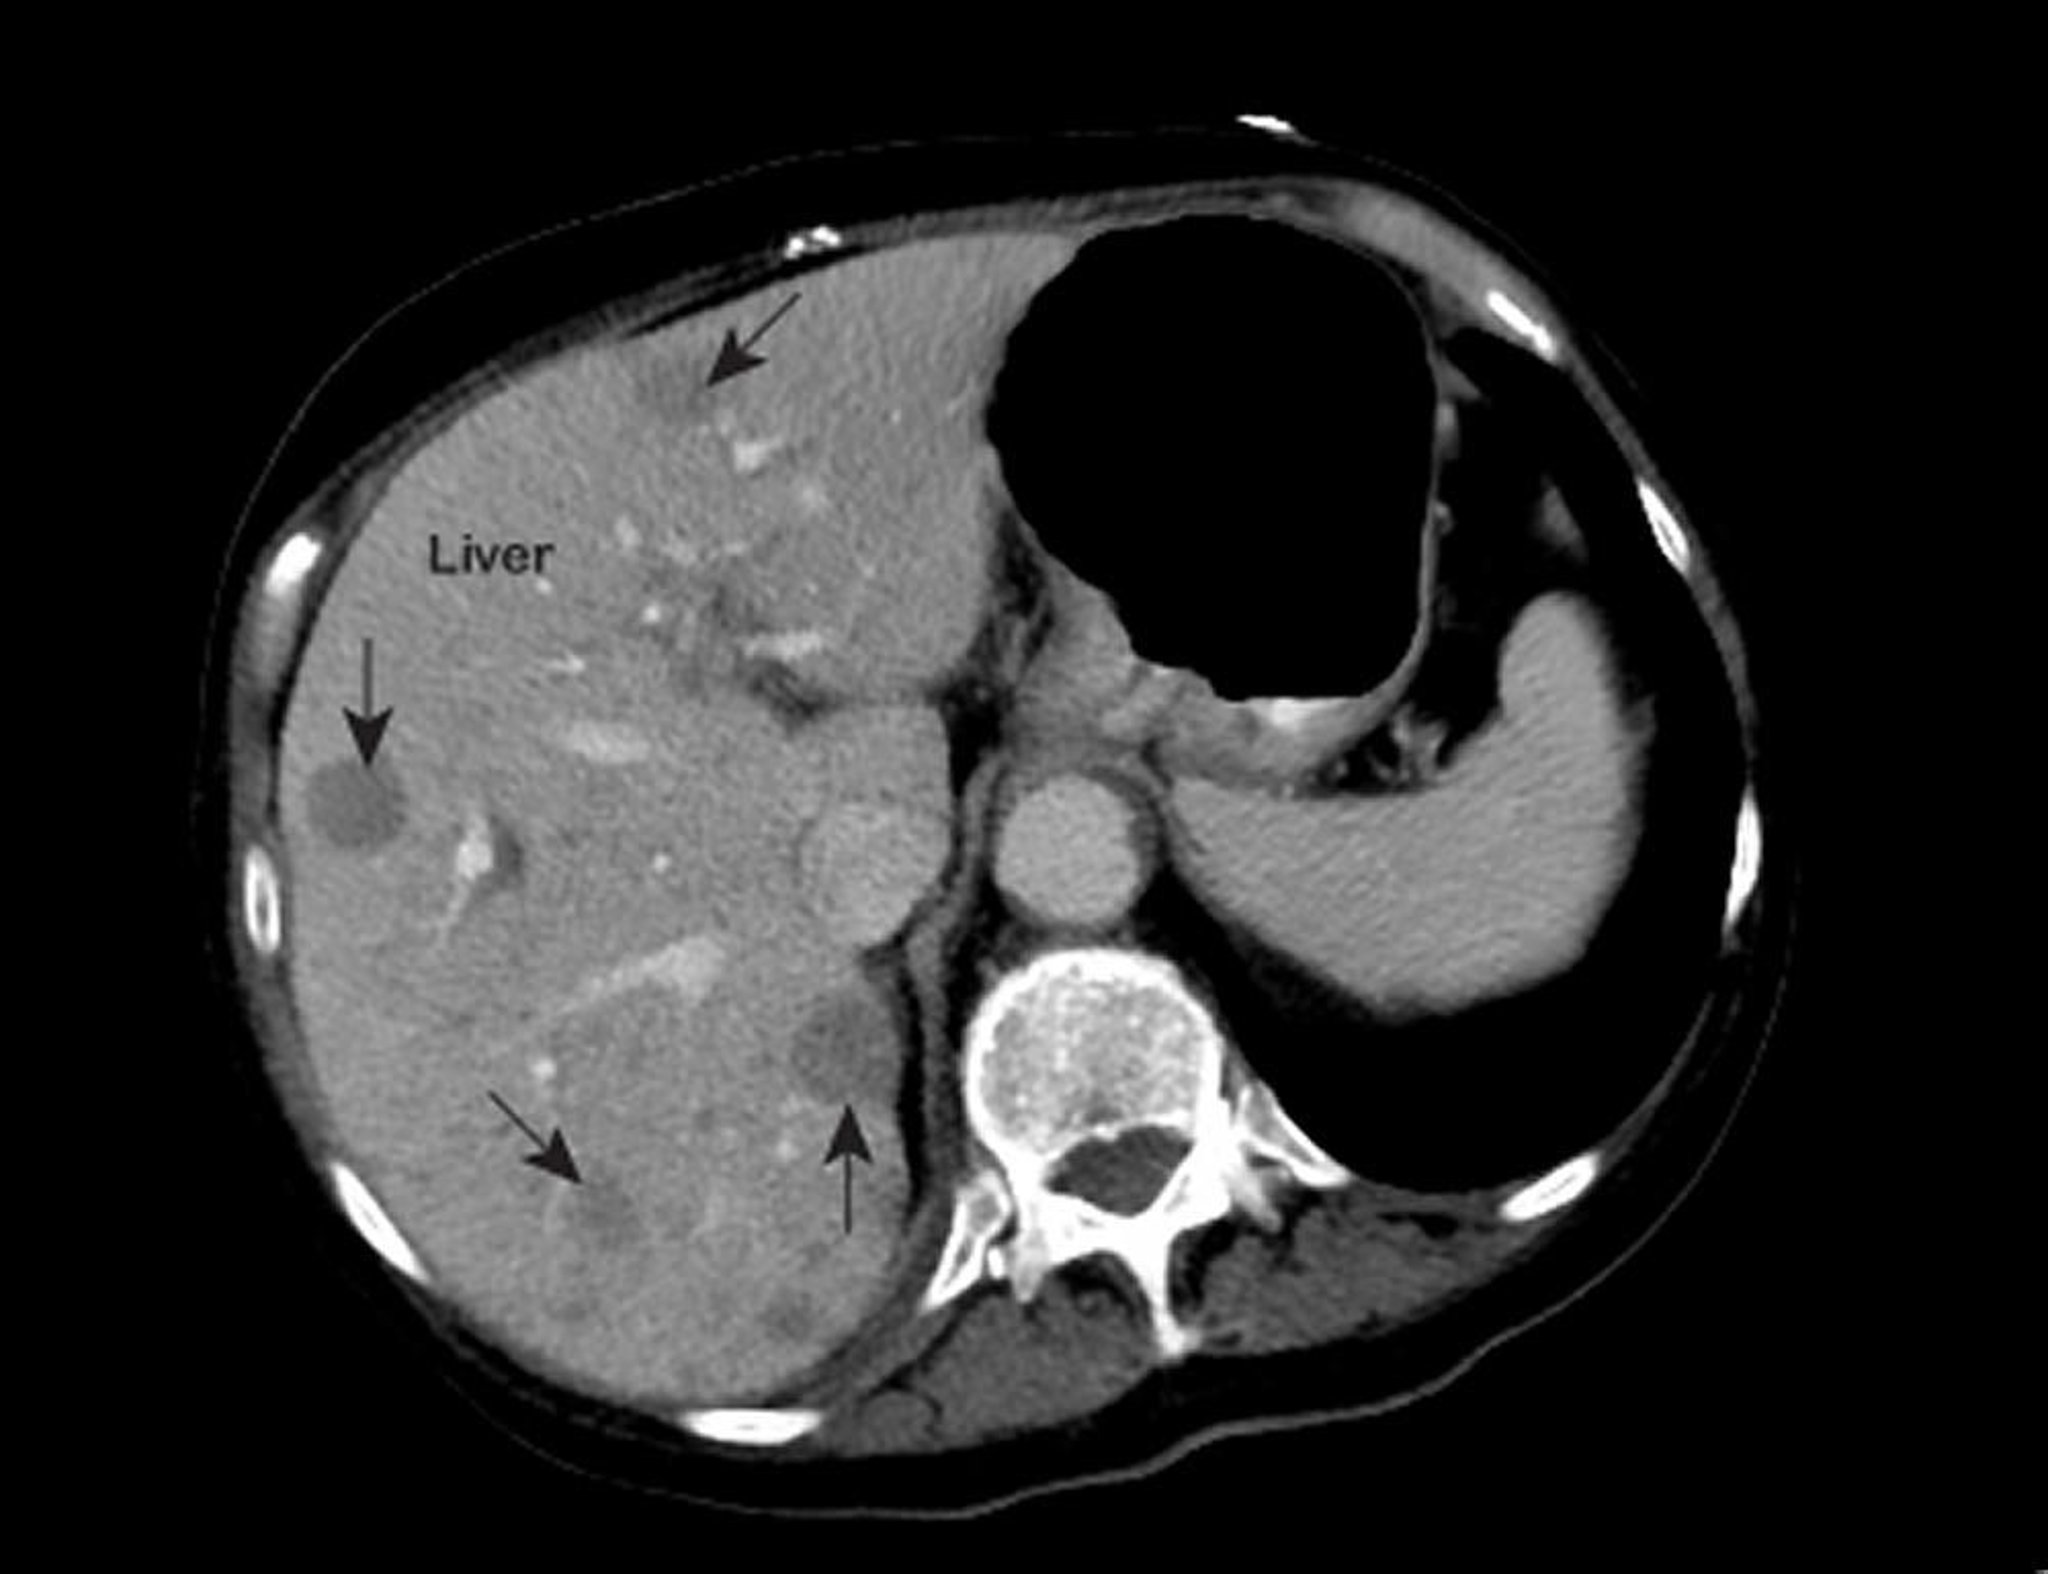

Tumore epatico metastatico

Un referto anomalo alla risonanza magnetica (RMI) del torace mostra lesioni (indicate con le frecce) intraepatiche. Questi riscontri sono caratteristici di un tumore epatico metastatico.

Foto offerta cortesemente dal Dott. Patrick O’Kane, MD.